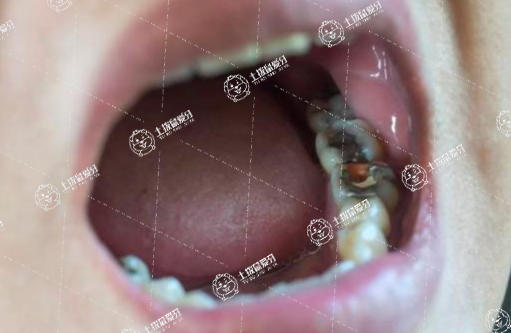

補(bǔ)牙是否需要打麻藥的話,要分情況,比方說蛀牙比較淺,沒有感覺或者一點點敏感,那么就不需要打麻藥的。如果說蛀牙比較深了這種情況的話,看個人承受能力,有些人可能不耐痛,那這種的話是需要打麻藥的,如果有些人覺得還可以接受的,那就靠近牙神經(jīng)也不需要打麻藥。

需要根據(jù)實際情況確定,一般齲齒需要探查,深度較淺的不需要麻藥。如果較深,觸及牙髓需要麻藥。需要去正規(guī)的醫(yī)院口腔科進(jìn)行充填修復(fù)治療。意見建議:補(bǔ)牙后不要吃比較硬的食物的,要吃比較軟,易消化的食物,以免損傷到新補(bǔ)的牙齒。對于患者的情況,可以去附近的門診或者醫(yī)院請醫(yī)生檢查后聽取醫(yī)生的建議